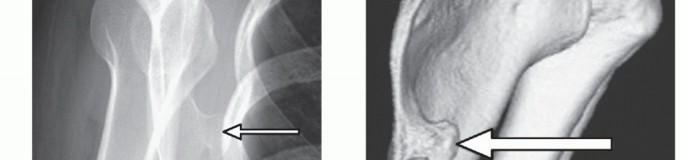

FIG 4 • A. A scapular Y view showing a prominent osteochondroma (arrow) of the body of the scapula, causing symptomatic snapping. B. A three-dimensional CT scan shows the bony anatomy in more detail. The arrow points to the same osteochondroma.

FIG 4 • A. A scapular Y view showing a prominent osteochondroma (arrow) of the body of the scapula, causing symptomatic snapping. B. A three-dimensional CT scan shows the bony anatomy in more detail. The arrow points to the same osteochondroma.

Radiologic studies should include an anteroposterior (AP) and tangential (Y) views of the shoulder to identify bony abnormalities in the scapula and ribs (FIG 4A).

A computed tomography (CT) scan may be needed for more bony definition. Its role, with or without three-dimensional reconstruction, is still debated,19,25 but in patients with suspected bony skeletal abnormality, the CT scan might be helpful (FIG 4B).